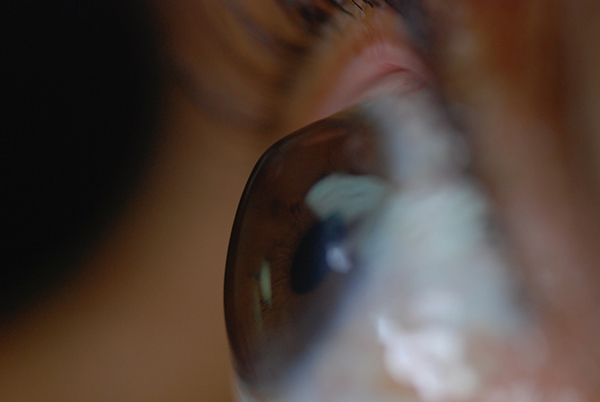

Keratoconus is a non-inflammatory, usually slow progressive eye disorder in which the normal spherical shaped cornea (the outer most transparent tissue/window of the eye) thins and progressively protrudes into a cone-like shape. This changed shape, is irregular and since the cornea is responsible for refracting most of the light entering the eye, an irregular cornea usually suffers from high refractive errors and especially high irregular astigmatism and therefore causes blurred and distorted vision.

Keratoconus is a non-inflammatory, usually slow progressive eye disorder in which the normal spherical shaped cornea (the outer most transparent tissue/window of the eye) thins and progressively protrudes into a cone-like shape. This changed shape, is irregular and since the cornea is responsible for refracting most of the light entering the eye, an irregular cornea usually suffers from high refractive errors and especially high irregular astigmatism and therefore causes blurred and distorted vision. Keratoconus can affect one or both eyes, it tends to progress less and in a slower rate if diagnosed after the age of 25. However it can occur during puberty and early management is very important. Keratoconus is the most frequently seen corneal ectasia with a prevalence of 1 in 1000. This number is thought to be much higher around our region, the region of the eastern Mediterranean. The cause of all corneal ectasias is not really known, even though there is most certainly a genetic predisposition for their inheritance.